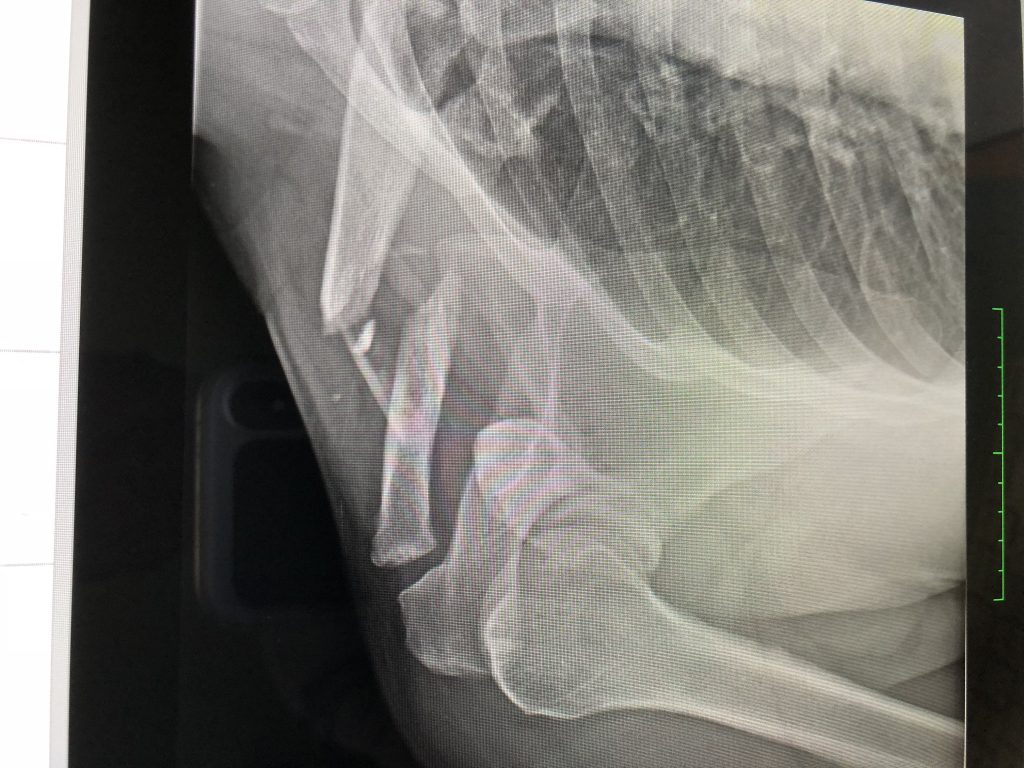

I broke my collarbone in several places after taking a hard fall from my electric longboard. I initially saw another orthopedic surgeon, but his empathy left something to be desired. Upon getting a second opinion with Dr. DiFelice, I knew I had come to the right doctor. His team took exceptional care of me and Dr. DiFelice took the time to explain my options and recommend surgery as the best course of action.

It took two plates and 13 screws to repair my collarbone. After seven weeks in a sling and with his team’s recommendation on a physical therapist; I can wholeheartedly say I’m Back in the Game!